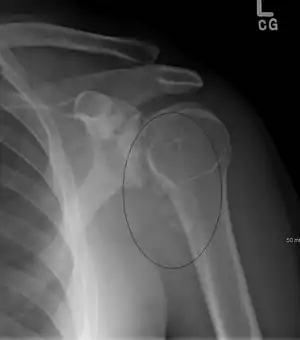

Typical finding is of multiple, smooth, oval-shaped calcified masses within the joint space or bursa. They have a characteristic popcorn-ball appearance of calcified cartilage. With serial imaging, masses may be found to change in size, disappear, or migrate to recessed areas of the joint. They may pass from the main joint cavity into a neighboring synovial cyst. For this reason, a mass may not be appreciated within the actual joint space itself.

Additional radiographic findings include joint effusion and degenerative changes such as joint space narrowing, subchondral sclerosis, and osteophyte formation.

Intra-articular bodies in SOC typically have popcorn calcification, with a dense sclerotic border with radiolucent central region. This distinct radiographic appearance sets it apart from other causes of intra-articular bodies. Number and size of intra-articular bodies can prove helpful as well. SOC typically presents as multiple intra-articular bodies. Few or isolated intra-articular bodies are more consistent with trauma or osteoarthritis.